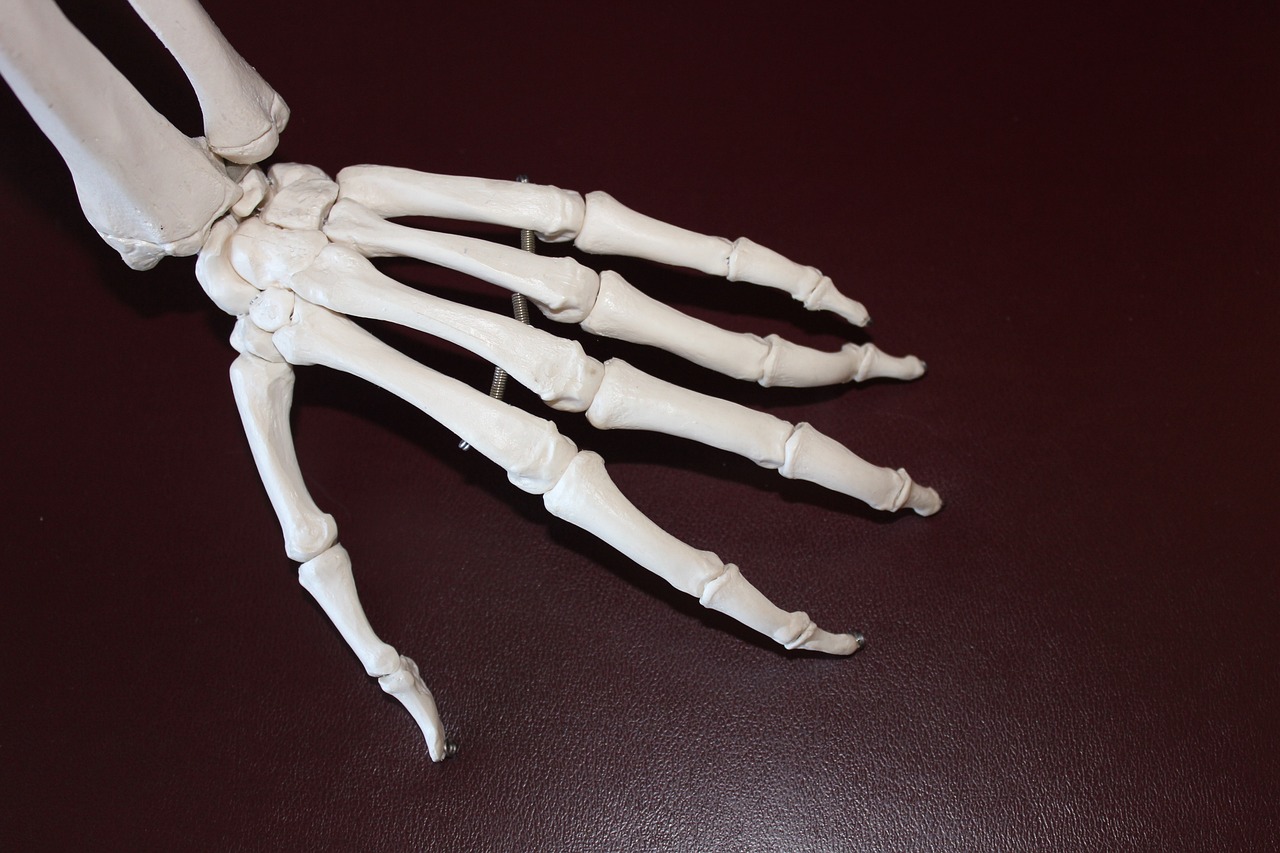

관절 건강은 나이가 들수록 신경 써야 할 중요한 건강 요소입니다. 관절은 신체의 움직임을 가능하게 하는 역할을 하며, 이를 지키기 위해서는 올바른 식습관, 적절한 운동, 그리고 필요한 영양제를 섭취하는 것이 중요합니다. 아래에서는 관절 건강을 유지하고 개선하는 데 도움을 줄 수 있는 방법들을 소개합니다.

5. 비타민 D와 칼슘

• 관절뿐 아니라 뼈 건강을 위해 필수적인 영양소입니다.

• 햇볕을 쬐거나, 유제품 및 보충제를 통해 섭취하세요.